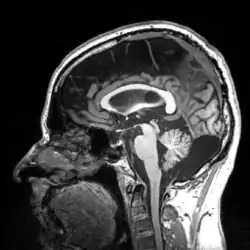

More recently, computed tomography has played a large role in reconstructing endocasts. The procedure is non-invasive and has the advantage of being able to analyze a fossil in record time with little risk of damaging the fossil under review. CT imaging is achieved through the application of x-rays to produce tomographs, or sectional density images, which are similar to the images produced during MRI scans.[8] CT scans use slices approximately 1 mm thick to reconstruct a virtual model of the specimen.[9] This method is especially useful when a fossil cranium is occupied by a natural endocast that cannot be removed without destroying the skeletal portions of the fossil. Because the cranium and its contents are of different densities, the endocranial cavity and its unique traits can be reconstructed virtually.[8]

Radiographic technique such as computed tomographic imaging, or CT scans, coupled with computer programming have been used to analyze brain endocasts from as early as 1906.[10] Recent development of advanced computer graphics technology have allowed scientists to more accurately analyze of brain endocasts. M. Vannier and G. Conroy of Washington University School of Medicine have developed a system that images and analyzes surface morphologies in 3D. Scientists are able to encode surface landmarks that allows them to analyze sulcal length, cortical asymmetries and volume.[11] Radiologist, paleoanthropologists, computer scientists in both the United States and Europe have collaborated to study such fossils using virtual techniques.[10]

Recent studies by Emiliano Bruner, Manuel Martin-Loechesb, Miguel Burgaletac, and Roberto Colomc have investigated the connection between midsagittal brain shape and mental speed. This study incorporated human subjects' cognitive testing in relationship to extinct humans. They used 2D from 102 MRI-scanned young adult human for comparison. Such correlations are small, suggesting that the influence of midsagittal brain geometry on individual cognitive performance is negligible but still provides useful information of evolutionary traits of the brain. Areas associated with the parietal cortex appear to be involved in relationships between brain geometry and mental speed.[18]